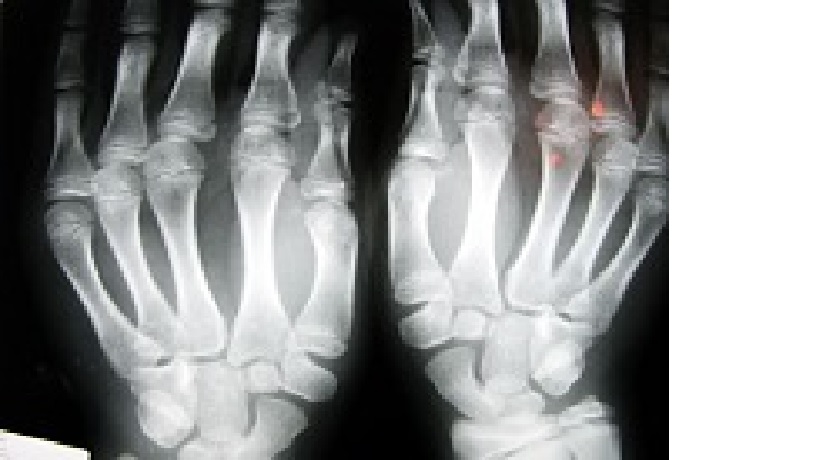

Największym problemem nie jest jednak sama osteoporoza, lecz złamania, do których ta choroba nieuchronnie prowadzi przy braku odpowiedniej profilaktyki i leczenia.

Osteoporoza występuje w Polsce u około 30 proc. kobiet i 8 proc. mężczyzn po 50. roku życia. Szacuje się, iż z powodu osteoporozy w Europie co 30 sekund dochodzi do złamania.